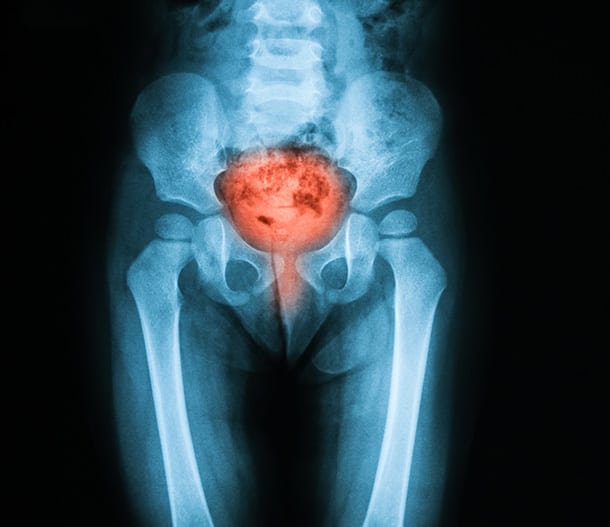

A urinary tract infection (UTI) happens when bacteria enter your urinary system—usually through the urethra—and multiply. Left untreated, UTIs can travel to the bladder or kidneys, causing serious complications. At InfiniHealth, we take a proactive, personalized approach to UTI care to protect your long-term health.

• High-Resolution Ultrasound: 3D imaging of your urinary system to detect structural abnormalities.